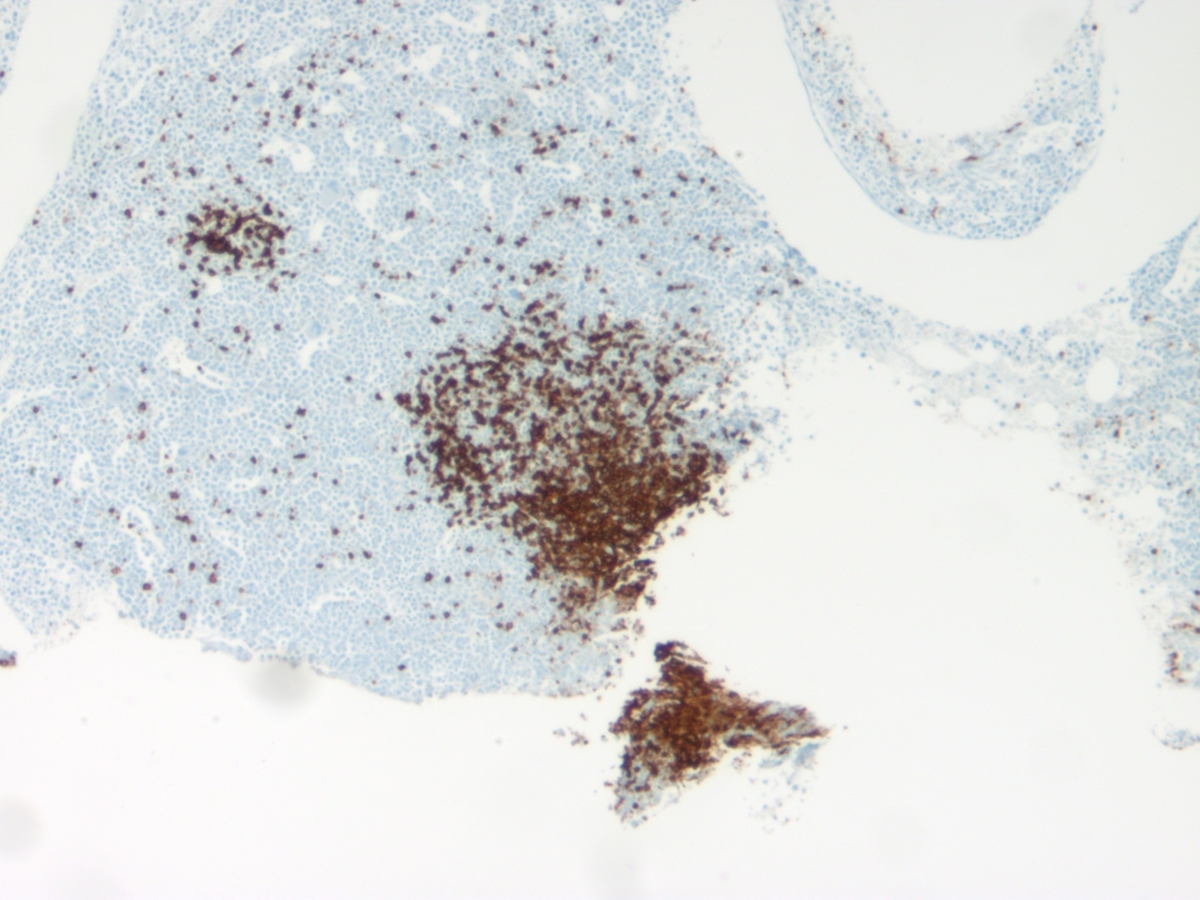

Immunohistochemistry performed on the bone marrow biopsy revealed that the lymphoid aggregates were a mixture of CD3+ T cells and CD20+ B cells with T cells predominating. There was no coexpression of CD5 or CD10 on the B cells.CYTOGENETIC FINDINGS

| Bone marrow biopsy CD3 | ![]() |

| Bone marrow biopsy CD20 | ![]() |